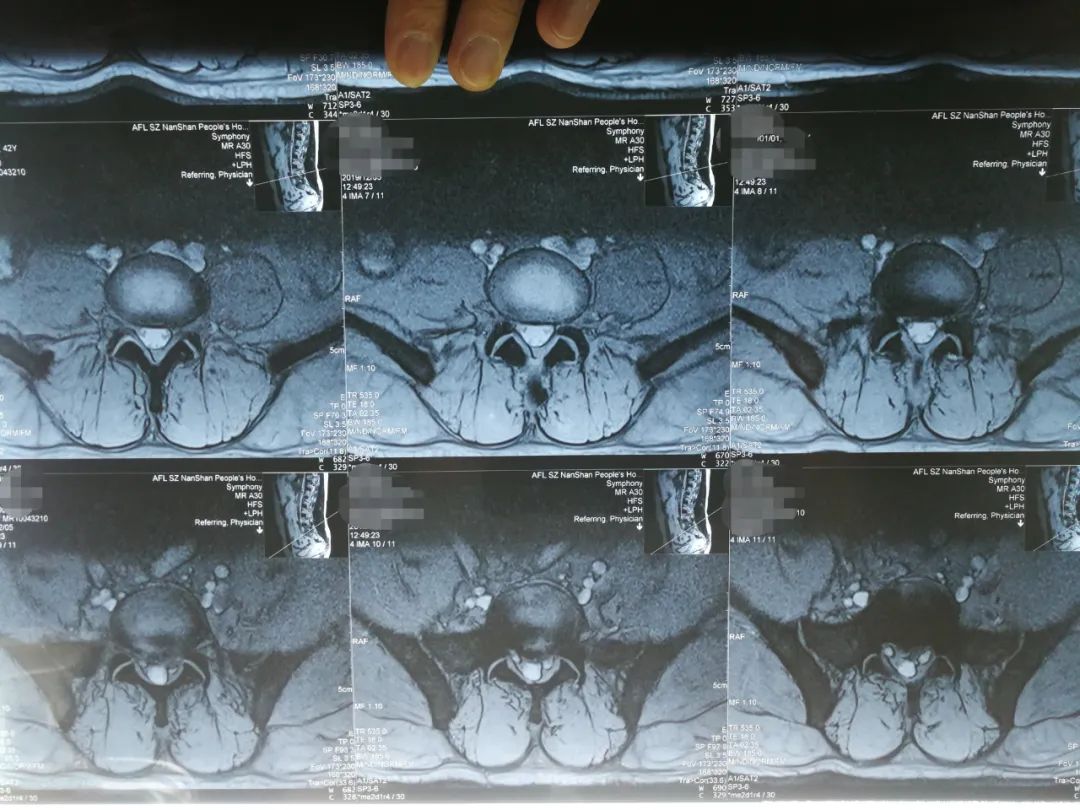

阅片

刘先生是典型的“腰椎间盘突出症(L5S1左后突出)”,伴有椎管狭窄的间歇性跛行症状,专科查体时最主要的体征是:

1、L5S1棘突左侧旁开1厘米处压痛、叩击痛并反射至左小腿后侧(骶1神经支配区);

2、仰卧挺腹试验未完成(因为疼痛);

3、左侧跟腱反射消失(骶1神经受压所致)。